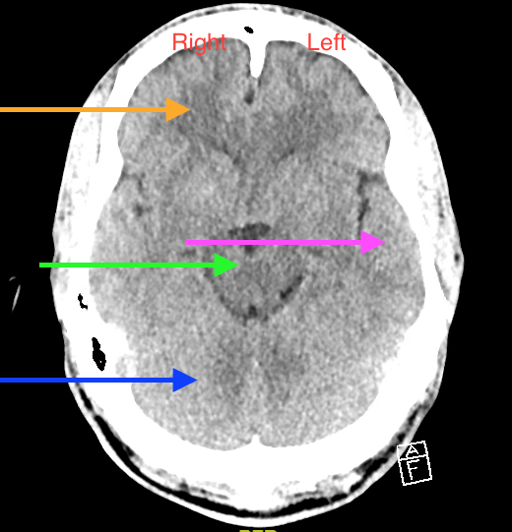

Now, let’s look at certain levels of the brain and identify key landmarks to help guide our reading. The right side of the brain will be on the left of your screen as marked in the below axial image and vice versa. The orange arrow in the below picture shows the right frontal lobe. The pink arrow shows the left temporal lobe; the green arrow shows the brainstem; the blue arrow shows the right cerebellum

Figure 2. Image courtesy of Baylor Scott and White Memorial Hospital–Temple, Texas.